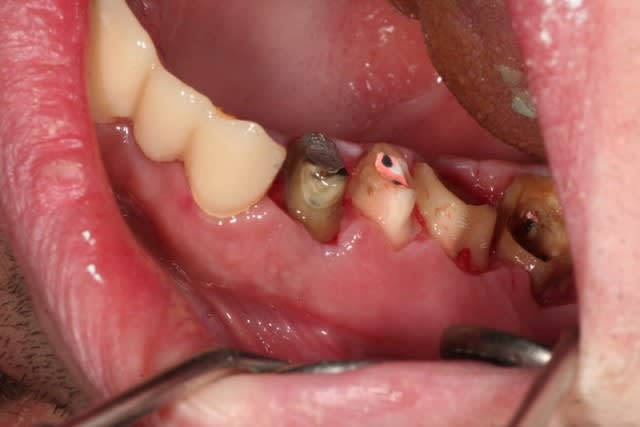

le traitement poursuit son bonhomme de chemin..

une vue du côté droit après élongation coronaire à une semaine...

à suivre..